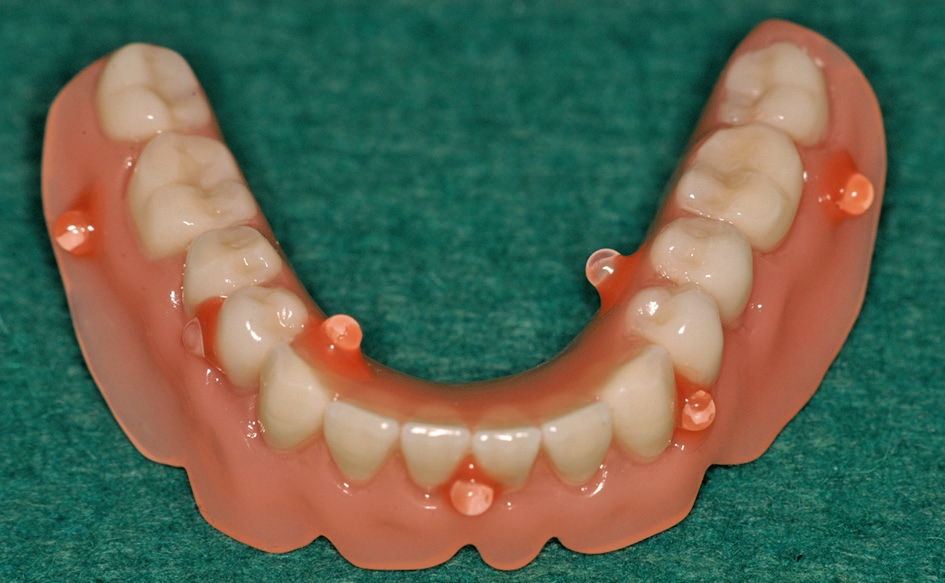

Abb. 17: Fertige Prothese mit dem integrierten Gehäuse.